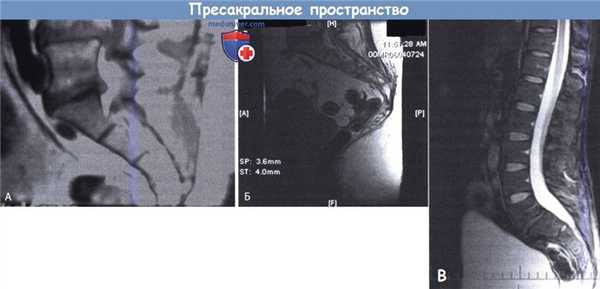

А. Пресакральное пространство: сосудистые и нервные образования.

LCIA — левая общая подвздошная артерия; LCIV — левая общая подвздошная вена;

LSA — латеральная крестцовая артерия; MSA — срединная крестцовая артерия; MSV — срединная крестцовая вена;

R — прямая кишка; RCIA — правая общая подвздошная артерия; RIIV — правая внутренняя подвздошная вена.

ST — симпатический ствол.

Б. Сагиттальный срез пресакрального пространства: R — прямая кишка; RF — ректосакральная фасция.

Авторы также разделили все пресакральное пространство на пять слоев (в направлении сзади наперед):

1) надкостница крестца,

2) париетальная пресакральная фасция,

3) ректосакральная фасция,

4) фасция автономных нервов и

5) собственная фасция прямой кишки.

Рабочее пространство следует формировать между париетальной пресакральной фасцией и ректосакральной фасцией в нижней части пресакрального пространства и между ректосакральной фасцией и фасцией автономных нервов в верхней его части.

А. Крупный сосуд, расположенный в пресакральном пространстве (МРТ).

Б. Спайки между кишечником и крестцом, крупный сосуд в пресакральном пространстве

В - Рубцовые изменения пресакрального пространства.